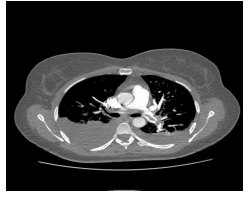

De acordo com esse achado, foi realizada uma toracocentese. A análise do líquido mostrou uma relação proteína pleural/sérica > 0,5 e DHL pleural/sérica > 0,6 com dosagem de ADA de 80 ui/L (VR: até 40 ui/L). Considerando essas informações, o diagnóstico é